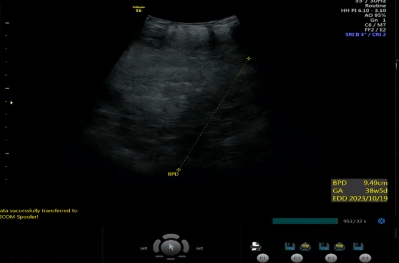

그냥 늘 하듯이, 아기 체중, 위치, 양수 양, 심박수 등을 확인하는데, 이때 아이가 혹시 역아 또는 횡아인지에 따라 제왕절개를 권유받을 수도 있어요!

저는 이번에 아기가.. 주수보다 거의 3주 가까이 머리가 크게 나왔는데;; 둘째니까 괜찮다고 하시네요^^;;;